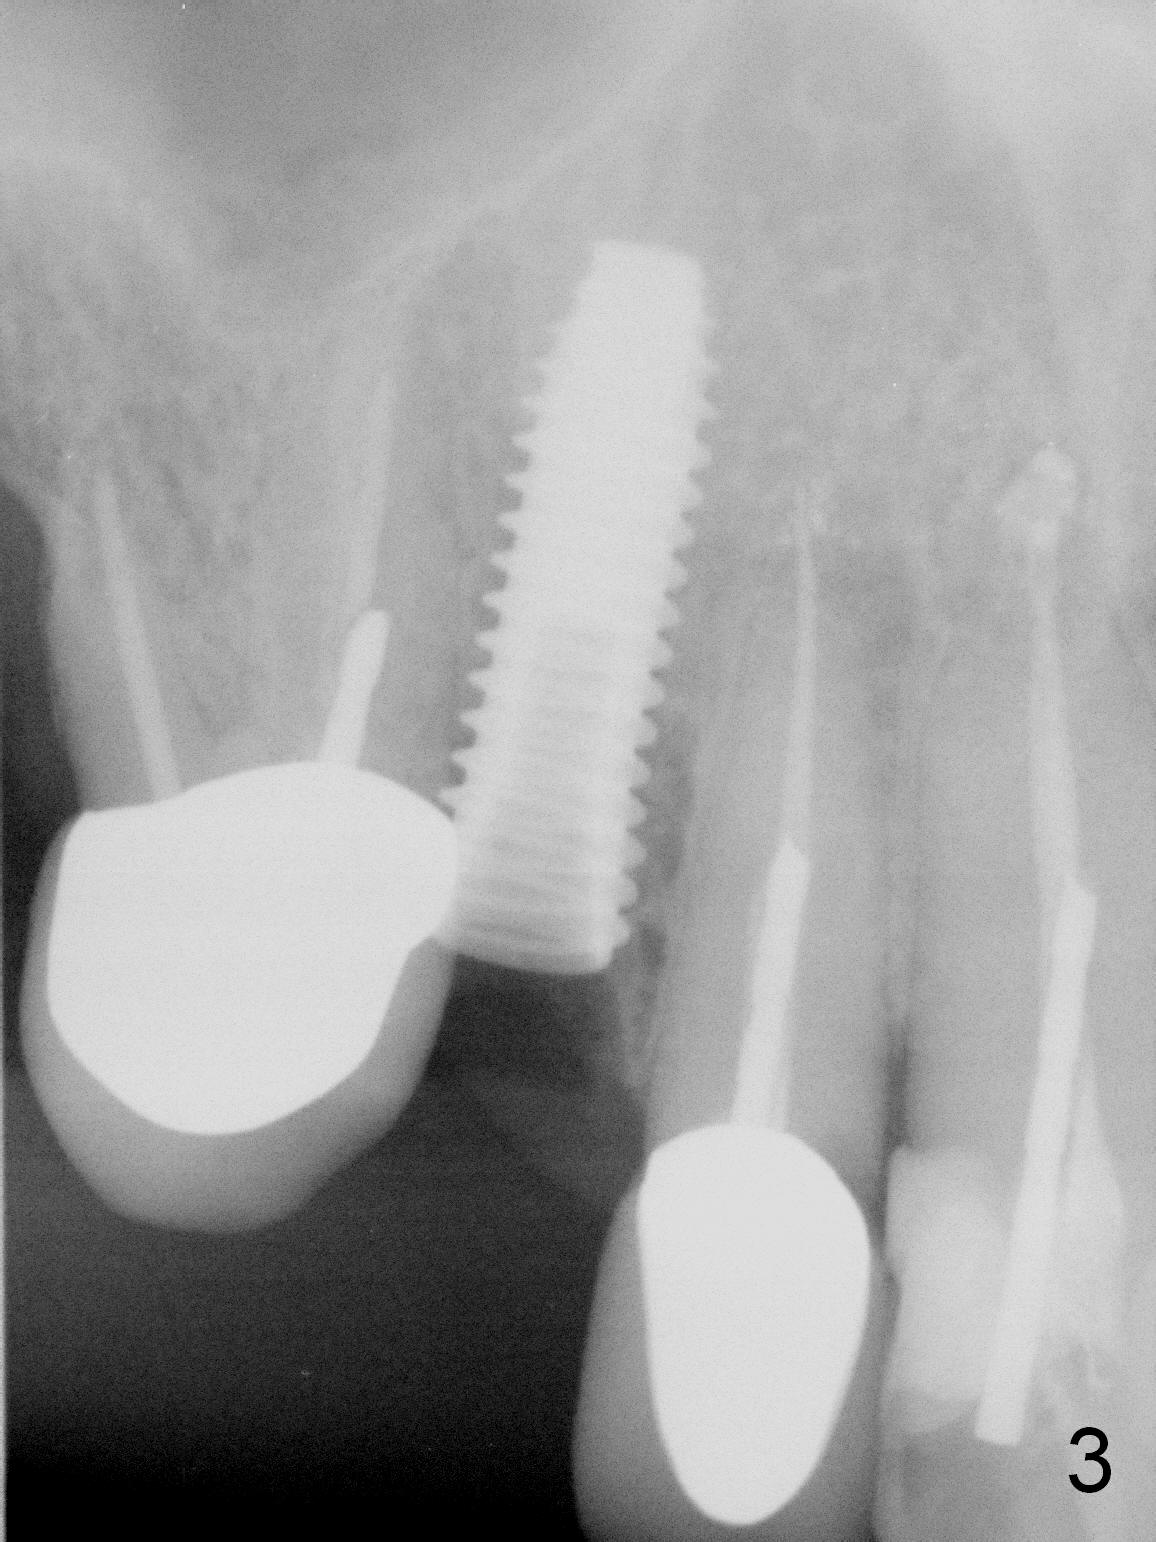

After extraction of the subgingival fractured upper right canine (Fig.1), the buccal plate is found to have been perforated at the apex. the root is measured 5x12 mm. Initial osteotomy with a 2 mm pilot drill shows that the bone is soft (Fig.2). After use of a 3.2 mm drill (underprep, normal drill size (3.7 mm)), a 4.5x15 mm implant is placed with insertion torque > 50 Ncm (Fig.3). The implant is further torqued until the implant plateau is 3 mm apical to the buccal gingival margin; a 5.5x5(3) mm abutment is placed (Fig.4,5 A). Osteogen plug is inserted into the apex of the socket, while the rest of gap is filled with mineralized cortical allograft and Osteogen. An immediate provisional (Fig.5,6 P) is fabricated to keep the graft in place, followed by periodontal dressing (Fig.6).